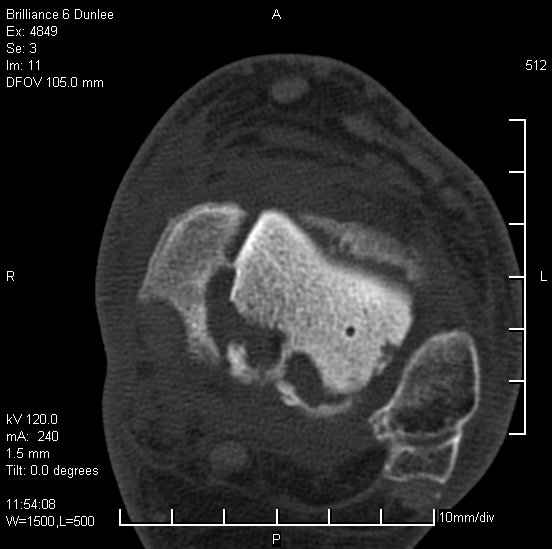

На лечении находится пациент 35 лет. Травма в сентябре 2008 г.- открытый вывих таранной кости

В день травмы ПХО, вправление вывиха, трансартикулярная фиксация. Рана зажила первично. С января нагрузка на конечность. С конца апреля- болевой синдром. На рентгенограммах и КТ признаки ас. некроза таранной кости, артроз подтаранного и голеностопного суставов.

У больного тотальный ас. некрох блока таранной кости, заинтересованы голеностопный и подтараный суставы. Эндопротезирование маловероятно на некротизированную кость. Изолированный подтаранный артродез таран не спасет.При артродезе всю некротизированную кость придется убрать.А далее замещение либо за счет большеберцовой кости, или удлинение на регенерате.